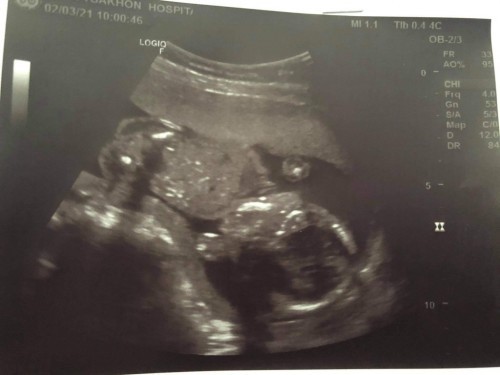

19Wอยากรู้เพศ คะ

สอบถามแม่ๆหน่อยคะไปซาวด์ ตอน19week แบบนี้พอเดาได้มั้ยคะว่า ญ/ช อยากถามประสบการณ์แม่ๆคะ😍